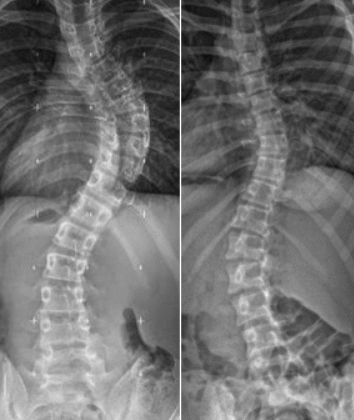

اعوجاج العمود الفقري (أو ما يُعرف بالجنف) هو انحناء جانبي غير طبيعي للعمود الفقري يظهر عادة في فترة البلوغ والنمو السريع، وغالبًا لا يكون له سبب محدد، لذلك يُطلق عليه “مجهول السبب”.

قد يكون الانحناء بسيطًا لا يُلاحظ بسهولة، أو متوسطًا يحتاج متابعة، أو شديدًا يتطلب علاجًا متخصصًا.

ويُقاس عادةً باستخدام زاوية كوب (Cobb angle) من خلال الأشعة السينية الكاملة للعمود الفقري أثناء الوقوف.

زاوية كوب (Cobb angle) هي الطريقة القياسية التي يُقاس بها مدى الانحناء في العمود الفقري.

يقوم الطبيب بتحديد الفقرتين الأكثر ميلًا في أعلى وأسفل الانحناء، ثم يقيس الزاوية بينهما على صورة الأشعة.

وتُستخدم هذه الزاوية لتصنيف شدة الحالة:

10 إلى 20 درجة: انحناء بسيط يحتاج فقط متابعة.

20 إلى 45 درجة: انحناء متوسط قد يحتاج إلى علاج طبيعي أو حزام اعوجاج العمود الفقري.

أكثر من 45–50 درجة: انحناء شديد قد يتطلب تدخلًا جراحيًا في بعض الحالات.

لكن من المهم معرفة أن زاوية كوب ليست العامل الوحيد في اتخاذ القرار، فالأطباء اليوم يعتمدون على الصورة السريرية العامة للحالة وليس على الأرقام فقط.